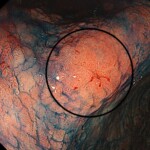

@胃レントゲン検査では発見できない早期胃がん

-150x150.jpg)